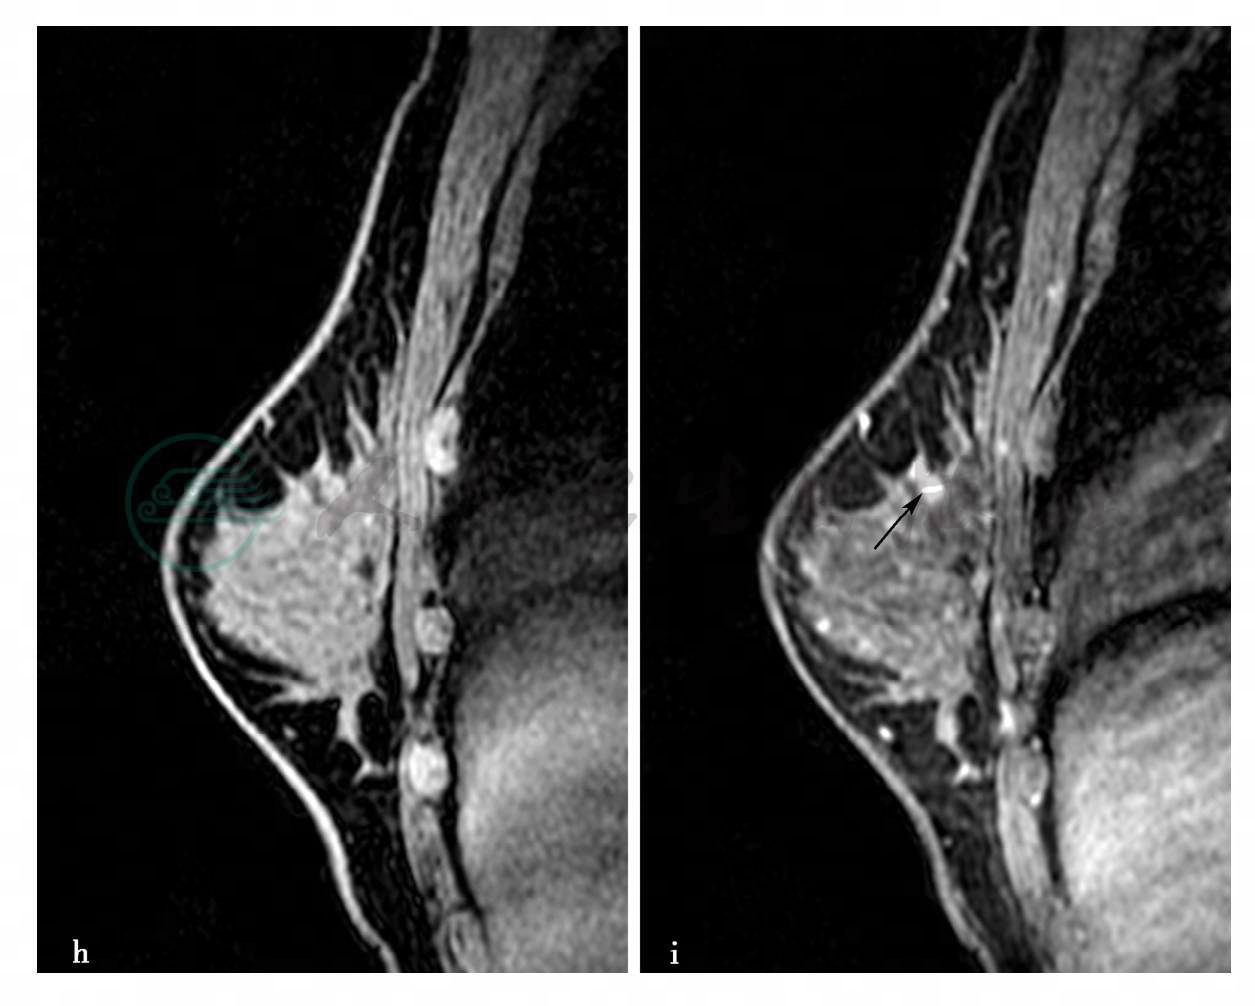

图3 图3h~k,分别为MRI动态增强前及增强后1min、2min、8min。图3l,MRI容积重建(VR)图(见文后彩图)。图3m,病变时间-信号强度曲线图。图3h~k,MRI显示右乳稍内上方(相当于X线片成簇钙化区域)局限异常强化病变,范围约2.8cm×2.3cm× 1.6cm。图3m,多点测量时间-信号强度曲线呈平台型和轻度流出型

病例1,(右乳腺)导管原位癌,以粉刺型及低乳头状型为主,核分级Ⅱ级。